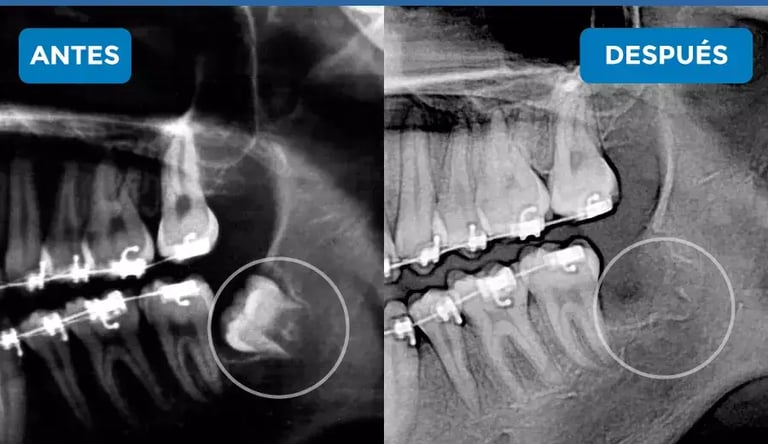

1️⃣ Valoración clínica y diagnóstico de la complejidad de cada muela. (Radiografia Panoramica) apoya el diagnostico.

Cuando la cordal está incluida, en mala posición o cerca de nervios, la valoración y el procedimiento se realizan con cirujano maxilofacial, experto en cirugías complejas y controladas.